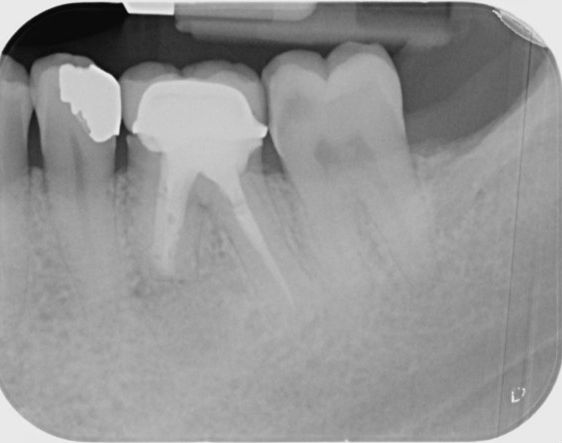

LR6: Root canal retreatment & internal root resorption management and cuspal coverage

Post Removal

12-Month Healing